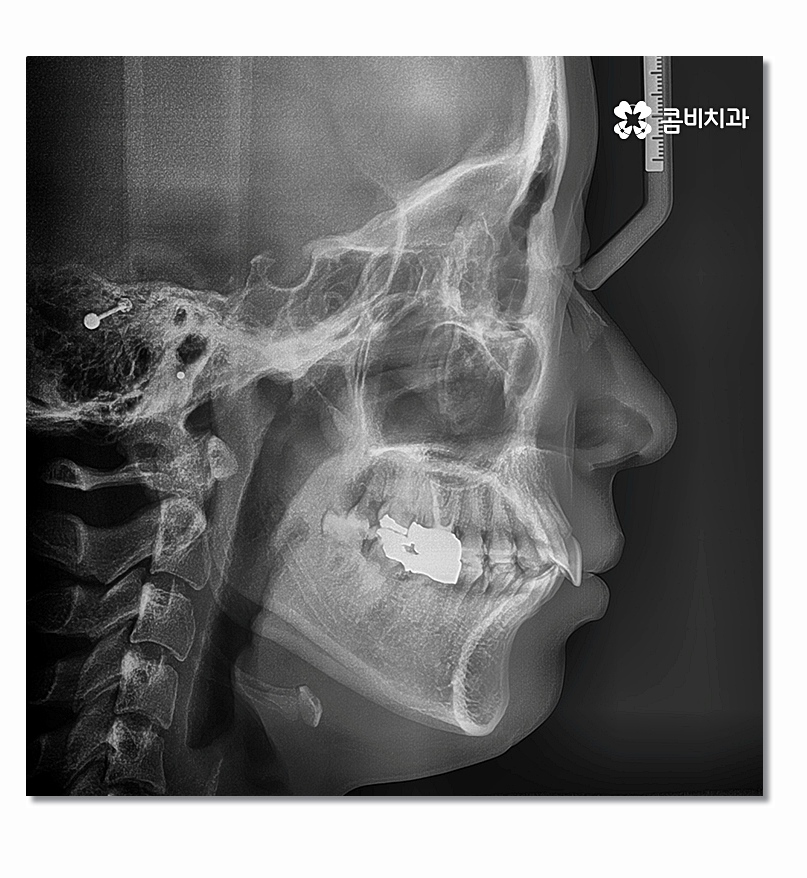

돌출입을 개선하기 위해서는 기본적으로 앞니의 각도와 배열, 위치 등의

조절이 필요하며 발치를 해야 하는 경우 보편적으로 송곳니 옆

작은 어금니를 발치하여 치아의 이동 공간을 확보하는 경우가 많다고 할 수 있어요.

치아의 심미성은 앞모습뿐 아니라 측면 그리고 자신의 얼굴과

자연스럽게 어울리는지 등을 함께 살펴야 하기 때문에

얼굴 변화를 기대하면서 치아교정을 결심하시는 분들도 많이 있는데요.

기본적으로 돌출입치아교정 치료 과정에 이러한 전체적인

부분을 고려해야 하면서 성장기에는 성장에 대한 부분까지

함께 생각해야 하기 때문에 의료진의 경험과 노하우가

매우 중요할 수밖에 없는 진료 분야라고 할 수 있어요.